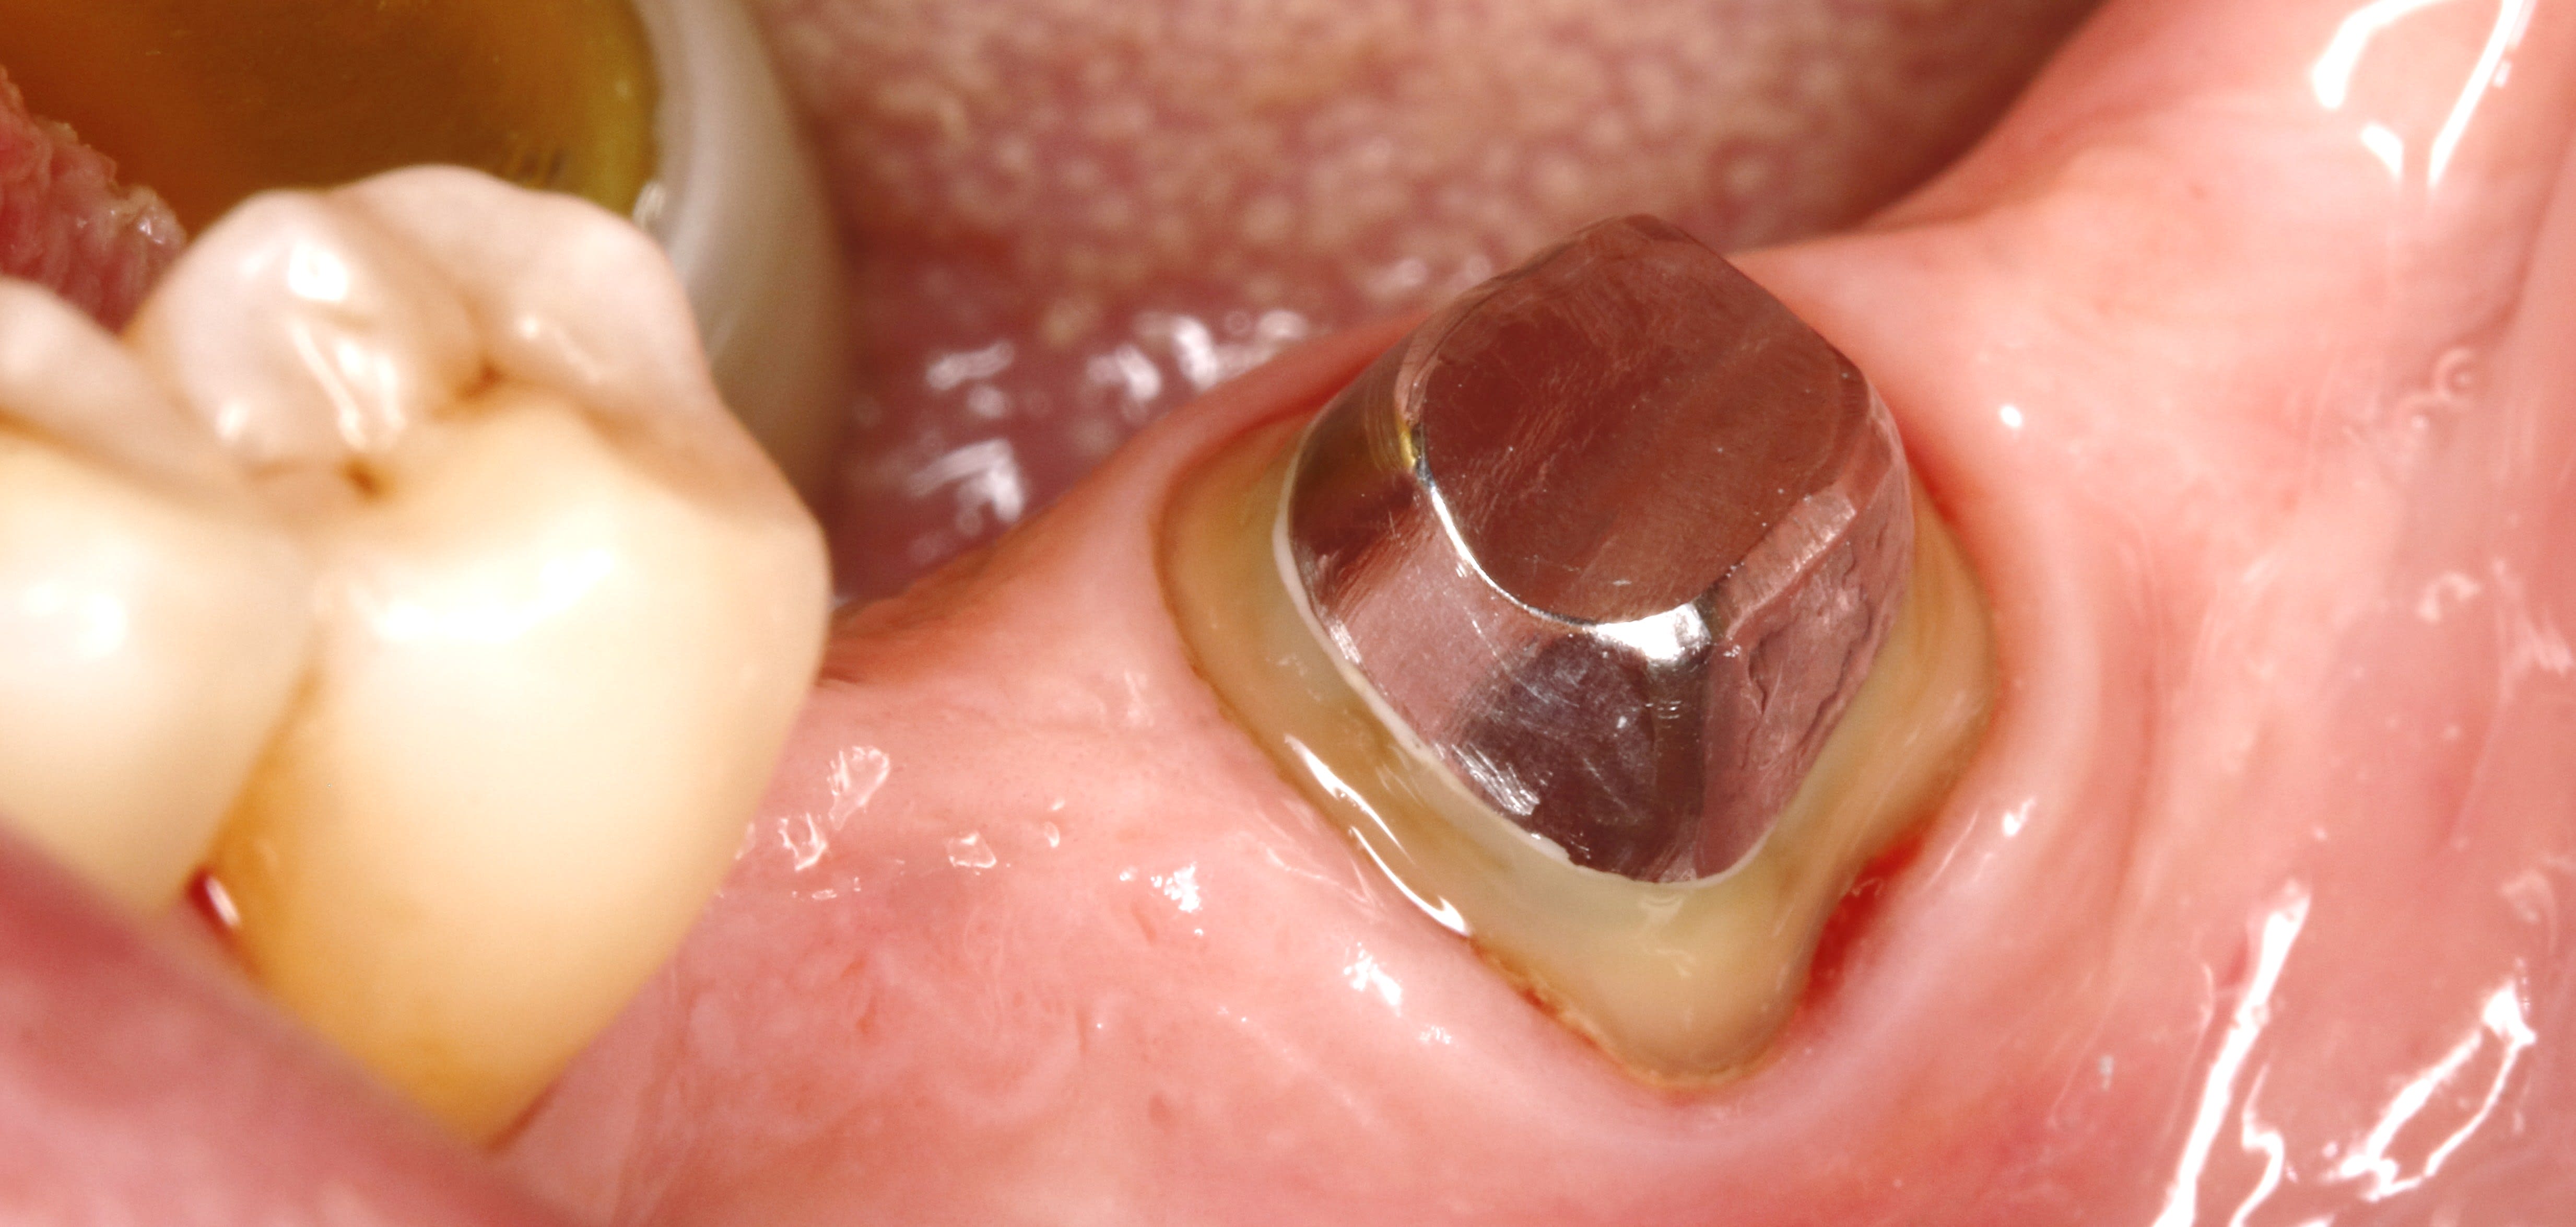

bien justement la voilà la 37 , je l ai vu aujourdhui .

la radio est belle , , je n' arrive pas a la mettre dessus avec ces putains de enregistrer sous , sous quoi ? je ne sais pas ,

bref tu peux me faire confiance , et en photo ça donne ça .

la gencive est belle et j'ai pris l empreinte .